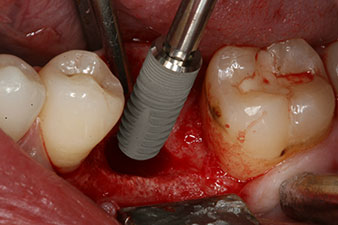

However, six weeks after the extraction incomplete ossification was found after preparation of the mucoperiosteal flap in the region of the former mesial alveolus.

The implant was placed as planned after thorough removal of the granulation tissue (blueSky, bredent).

The torque used for the machine-driven placement was 43 Ncm. In addition, after screwing a measuring post (SmartPeg) specially matched to the implant, the ISQ value was measured with the probe of the W&H Osstell ISQ module.

This module is an optional extra for the W&H Implantmed and is docked to the implantology motor (see Fig. 11). The dimensionless ISQ value immediately after insertion was 64 orovestibular and 68 mesiodistal (maximum value = 100).

These values could have indicated open healing or even immediate restoration. Due to the insufficient crestal bone volume at the implant, the region was augmented with the bone chips collected during preparation of the implant bed and sutured to exclude saliva.